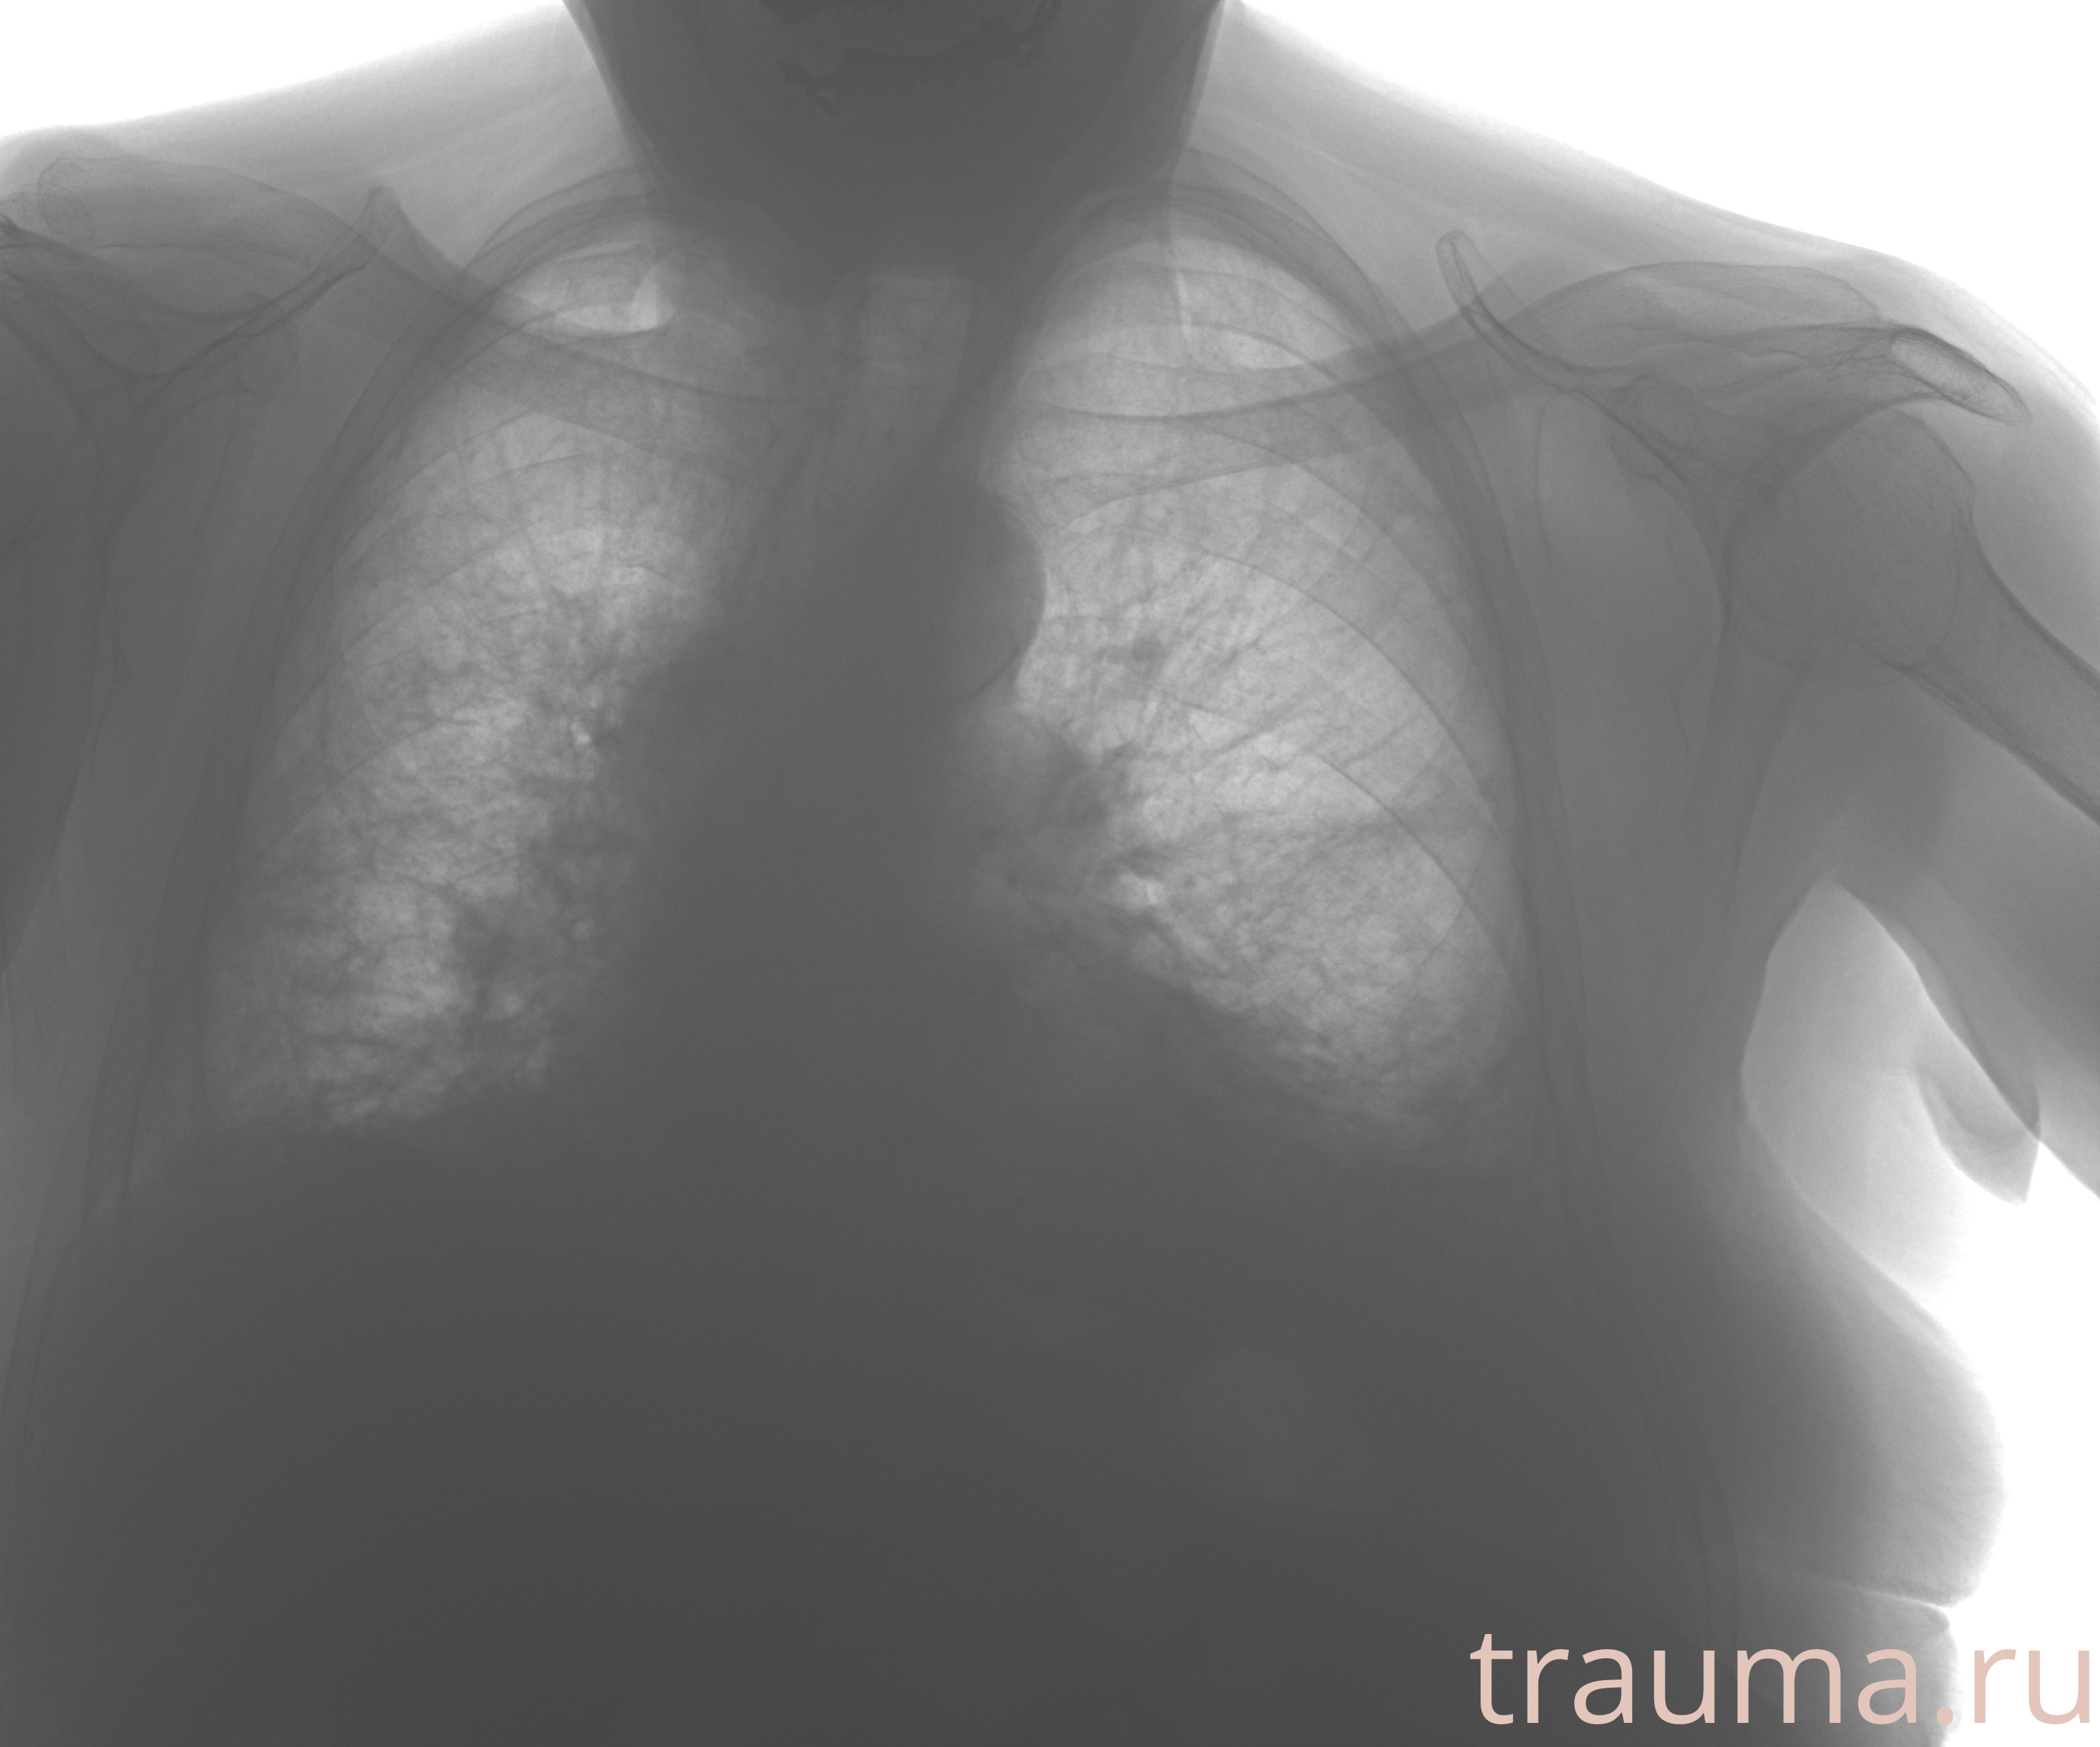

Рентген на дому: по вашему адресу приезжает врач-рентгенолог, травматолог-ортопед с мобильным рентгеновским аппаратом, проводит диагностику травмы или заболевания, делает необходимые рентгенограммы, дает рекомендации по дальнейшему лечению. Получить качественные снимки в домашних условиях возможно благодаря уникальной методике, разработанной МосРентген Центром для института  Склифосовского

при переломе шейки бедра и пневмонии от компании МосРентген Центр - партнера Института имени Склифосовского